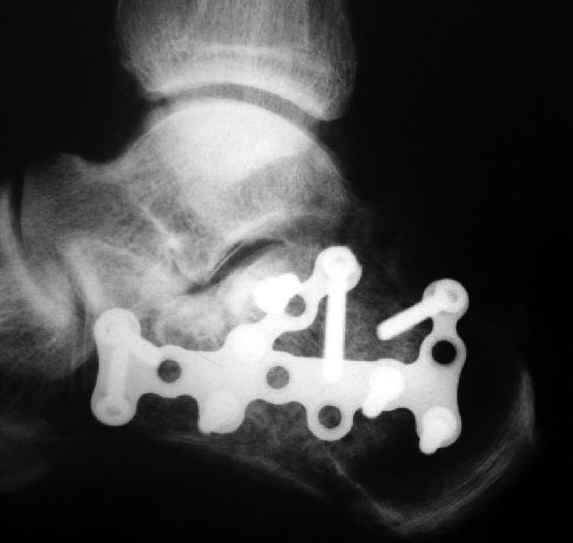

Очень хорошее впечатление осталось после использования выпускаемой для остеосинтеза пяточной кости АО реконструктивной пластины с угловой стабильностью. В России ее продает Синтез Матис.

Окончательная фиксация спицами, пяточными пластинами (5) , в последнее время стали применять крючковидные пластины (ДЕОСТ) (6,6a).